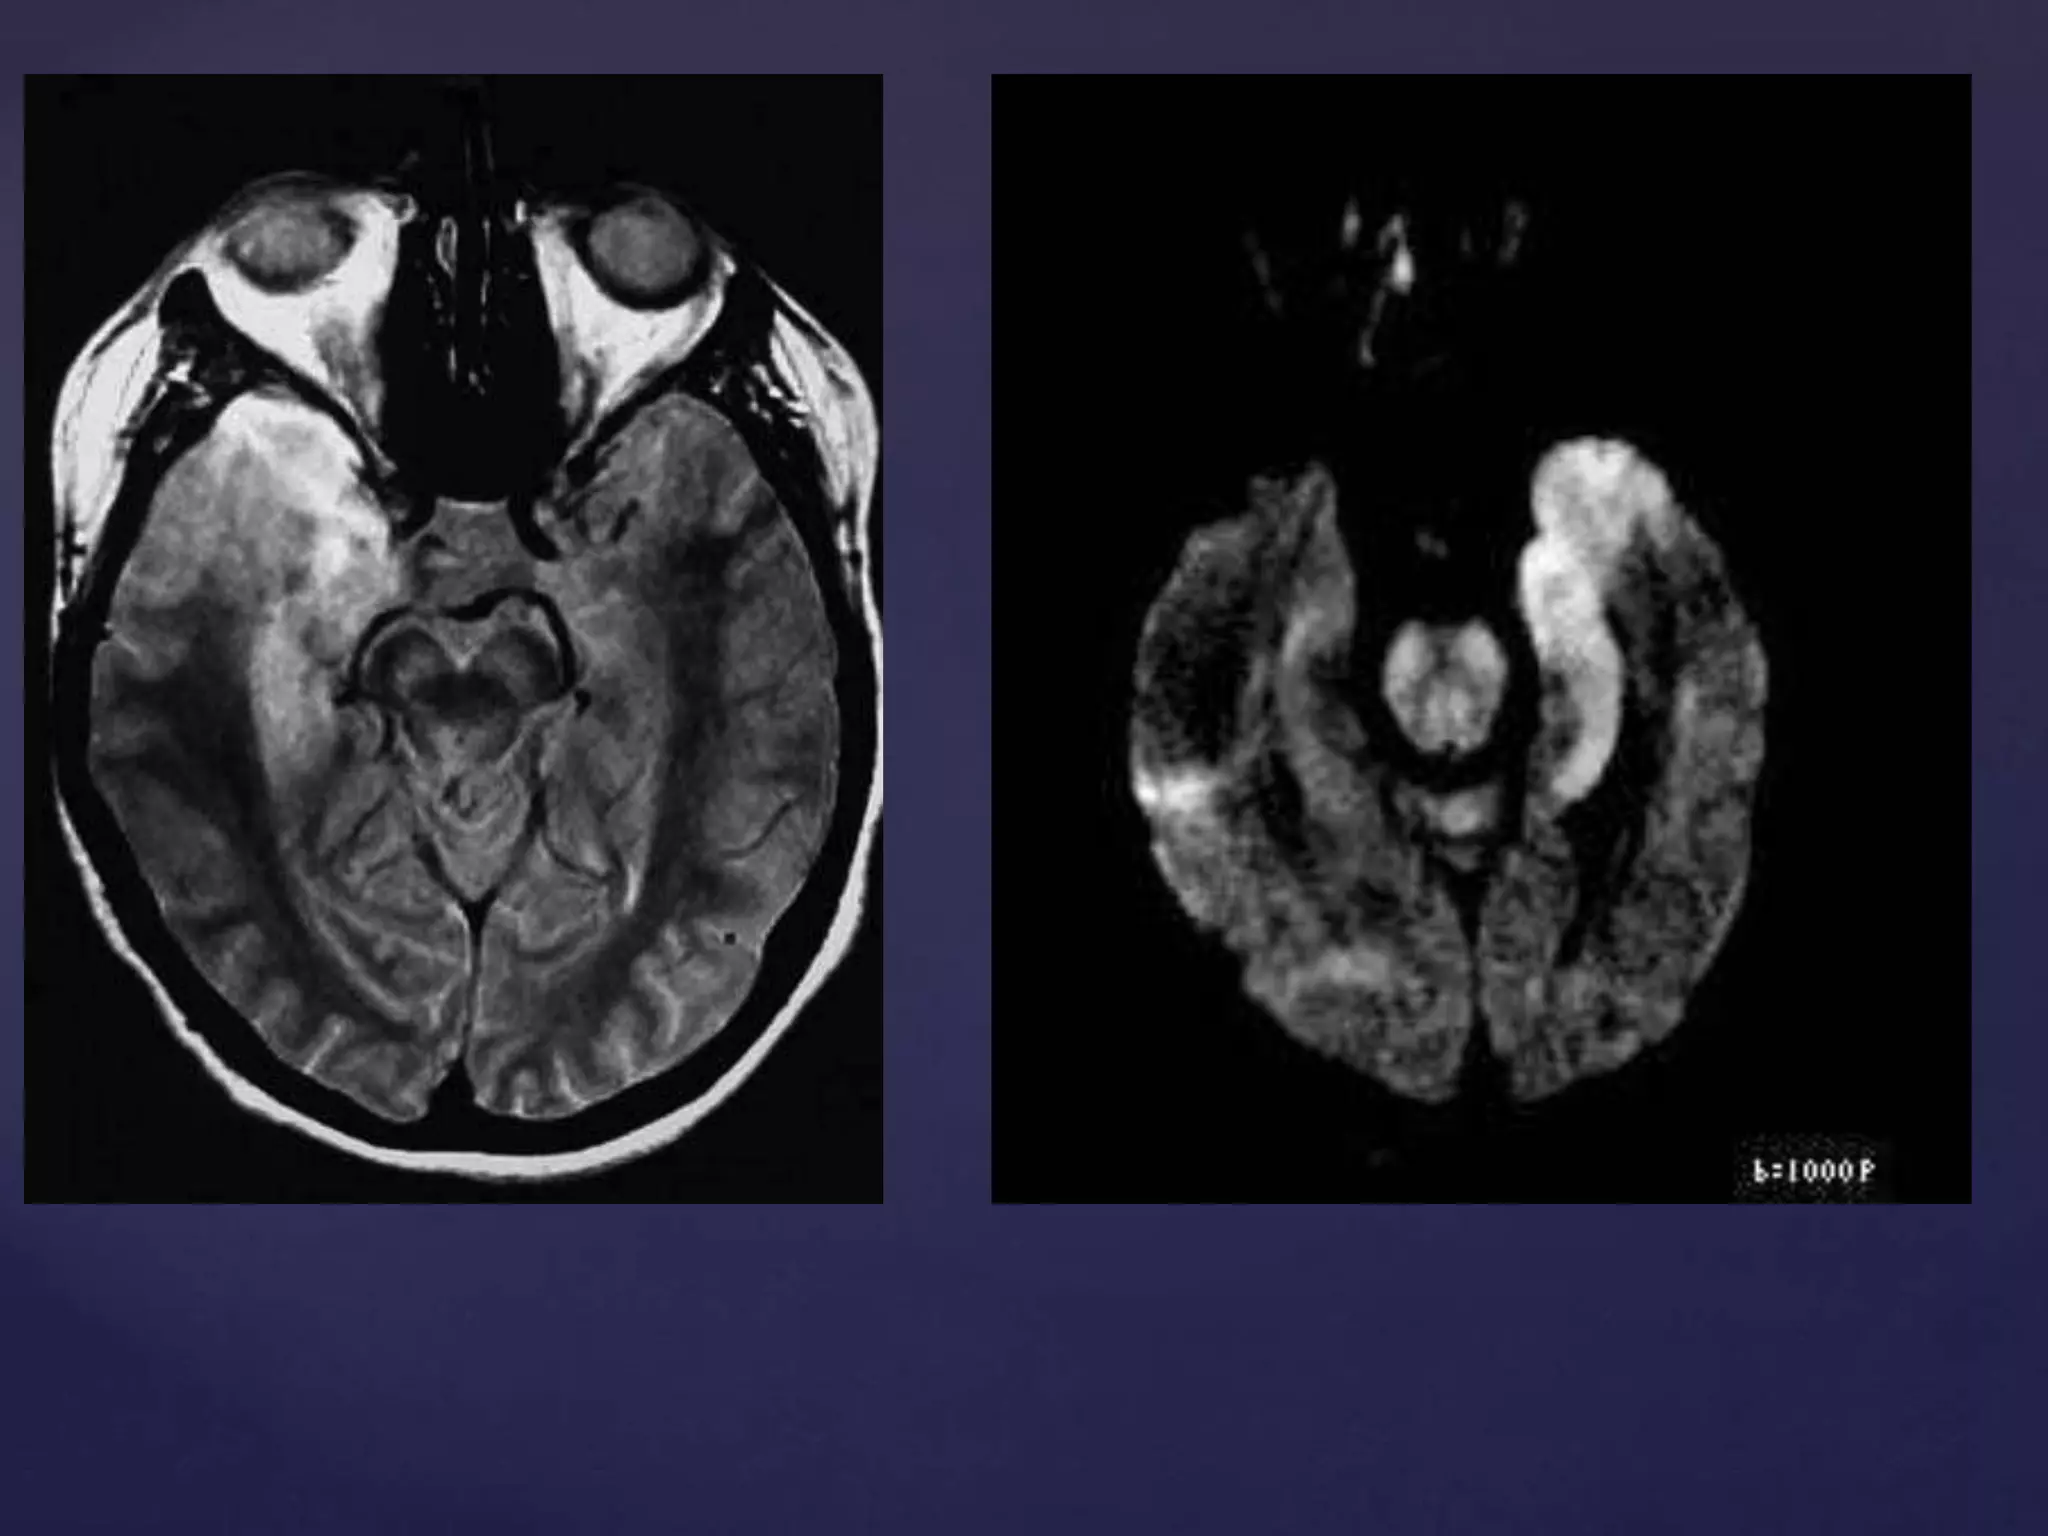

MRI

1. Noninvasively establish many of the potential alternative diagnoses

of HSE.

2. Abnormalities are found in 90% of patients with HSE; MRI may be

normal early.

3. The inferomedial portion of the temporal lobe is most commonly

affected on MRI, sometimes in association with abnormalities of the

cingulate gyrus.

CT 1. Early diagnosisis difficult. If findings are present, they typically consist of subtle low density within the anterior and medial parts of the temporal lobe and the Island Of Reil (insular cortex). 2. If scanned later then the changes may become more apparent and even progress to haemorrhage. Contrast enhancement is uncommon during the first week of the disease. After that, a patchy low-level enhancement may be seen. MRI 1. Noninvasively establish many of the potential alternative diagnoses of HSE. 2. Abnormalities are found in 90% of patients with HSE; MRI may be normal early. 3. The inferomedial portion of the temporal lobe is most commonly affected on MRI, sometimes in association with abnormalities of the cingulate gyrus.